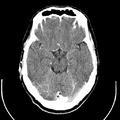

تصوير مقطعي حاسوبي

التصوير المَقْطَعي الحاسوبيX-ray computed tomography نظام تصوير بالأشعة السينية، يُسْتخدم لتصوير مختلف أجزاء الجسم مثل الرأس والقلب والبطن. ويستعين الأطباء بالتصوير المقطعي الحاسوبي على تشخيص الأمراض وعلاجها. وتسمى هذه التقنية أيضًا التصوير المقطعي المحوسب أو التصوير المقطعي المحوري المحوسب.

معرض الصور